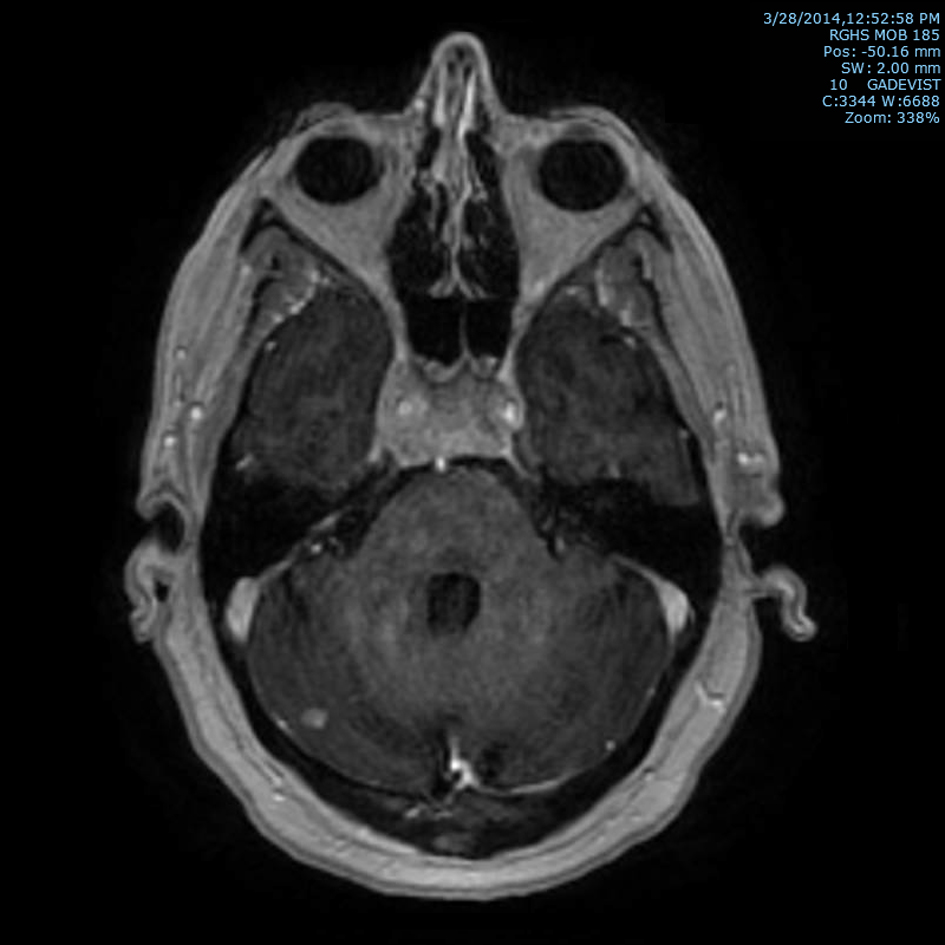

Subsequently, an MRI of the brain showed multiple intraaxial enhancing lesions involving the frontal lobes, cerebellar hemispheres, right occipital lobe in addition to an enhancing, expansile mass in the clivus with soft tissue component in the right cavernous sinus extending anteriorly into the sphenoid sinus (Fig. 1), superiorly into the sella and posteriorly into the pre-pontine cistern. There was encasement of the right internal carotid artery and presence of moderate associated vasogenic edema (Fig. 2). All of these findings were most suggestive of intracranial metastatic disease. Due to the presentation of multiple metastatic sites in the brain, it was not felt necessary to biopsy the cavernous sinus lesion.

![]() Click for large image | Figure 1. T1 post-contrast axial MRI image of brain showing marrow signal abnormality within the clivus with an expansile mass with soft tissue component in the cavernous sinus and right cerebellar metastasis. |